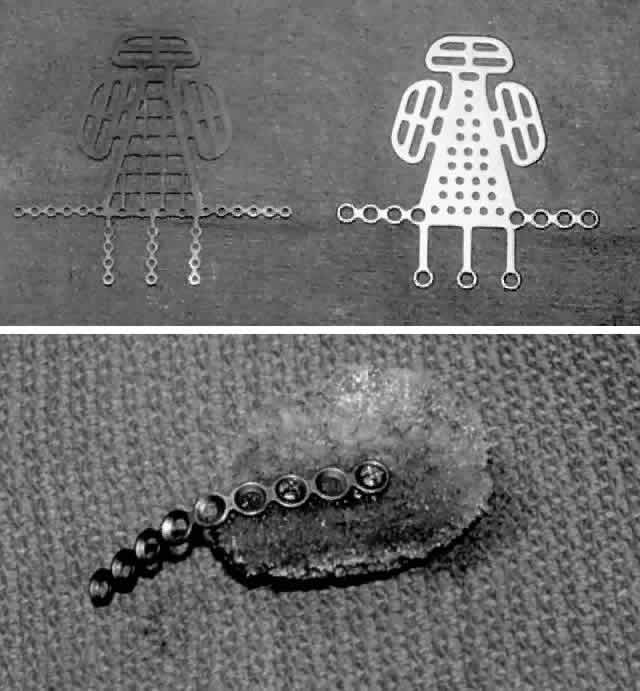

angled appearance.  Fig. 6. A. Metallic grid implants are used for rigid internal orbital fixation when

extensive disruption of two or more walls is present. B. Synthetic implants or bone grafts may also be rigidly fixed with a miniplate, which

is then “cantilevered” over the orbital rim. Fig. 6. A. Metallic grid implants are used for rigid internal orbital fixation when

extensive disruption of two or more walls is present. B. Synthetic implants or bone grafts may also be rigidly fixed with a miniplate, which

is then “cantilevered” over the orbital rim.